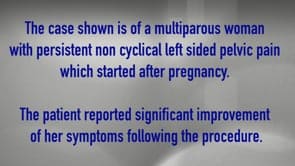

Vascular Complication during Laparoscopic Pelvic Surgery-Injury to inferior epigastric artery. (Video)